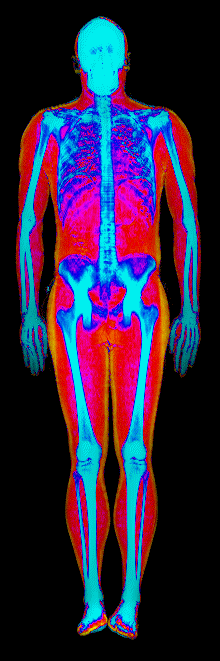

Each colorized scan shows the distribution of fat tissue (shown in warmer colors) and lean tissue (cooler colors) throughout the body. Compare your own DEXA scan to others in your range, or see what different body fat levels actually look like on a scan.

Male DEXA Scans by Body Fat %

15 to 20% body fat

20 to 25% body fat

25 to 30% body fat

30 to 35% body fat